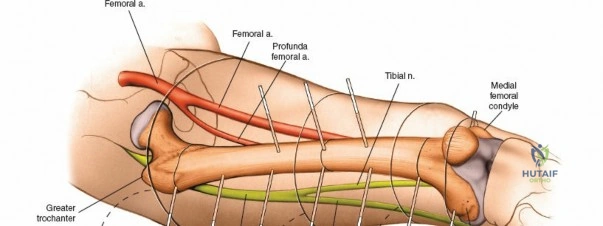

The humerus presents significant challenges due to the course of the radial nerve, axillary nerve, and brachial artery.

* Proximal Third: The safe zone is located laterally. Pins can be placed from lateral to medial, avoiding the axillary nerve, which runs transversely approximately 5 to 7 cm distal to the lateral acromion.

* Middle Third: This is the most hazardous region. The radial nerve spirals from posterior to anterior along the spiral groove. Anterolateral pin placement is generally safe if placed distal to the deltoid insertion, but open dissection to the periosteum is mandatory.

* Distal Third: The radial nerve pierces the lateral intermuscular septum to enter the anterior compartment. Pins are typically placed posteriorly or posterolaterally, directly through the triceps tendon or muscle belly, ensuring the radial nerve is protected anteriorly.

Humeral external fixation is most frequently utilized for damage control in polytrauma or for severe open fractures.

Proximal Humerus Pin Placement

Distal Humerus Pin Placement

1. The distal pins are typically placed posteriorly to avoid the radial nerve.

2. Make a longitudinal incision over the posterior aspect of the distal humerus, proximal to the olecranon fossa.

3. Split the triceps bluntly down to the periosteum.

4. Insert the tissue protector, pre-drill, and place the 5.0 mm pins from posterior to anterior.

5. Ensure the pins do not penetrate the anterior cortex excessively to avoid injury to the brachial artery or median nerve.

Construct Assembly

Connect the proximal and distal pins with pin-to-bar clamps and an 11 mm carbon fiber rod. Reduce the fracture under fluoroscopic guidance using manual traction. Tighten the clamps to secure the reduction. A biplanar construct can be created by adding anterior pins proximally and connecting them to the primary frame.